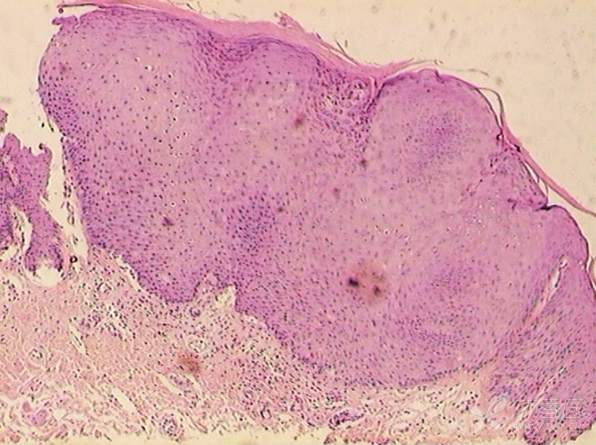

补充资料:组织病理,欢迎大家继续讨论哦~~